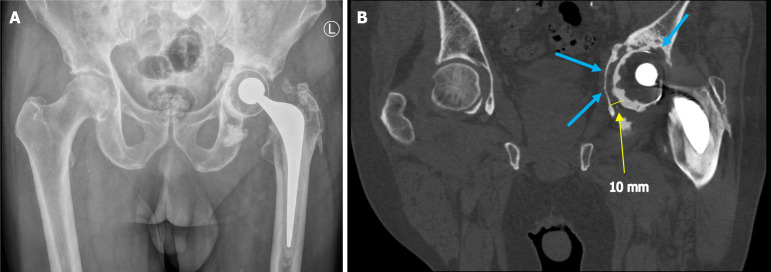

Abstract Image